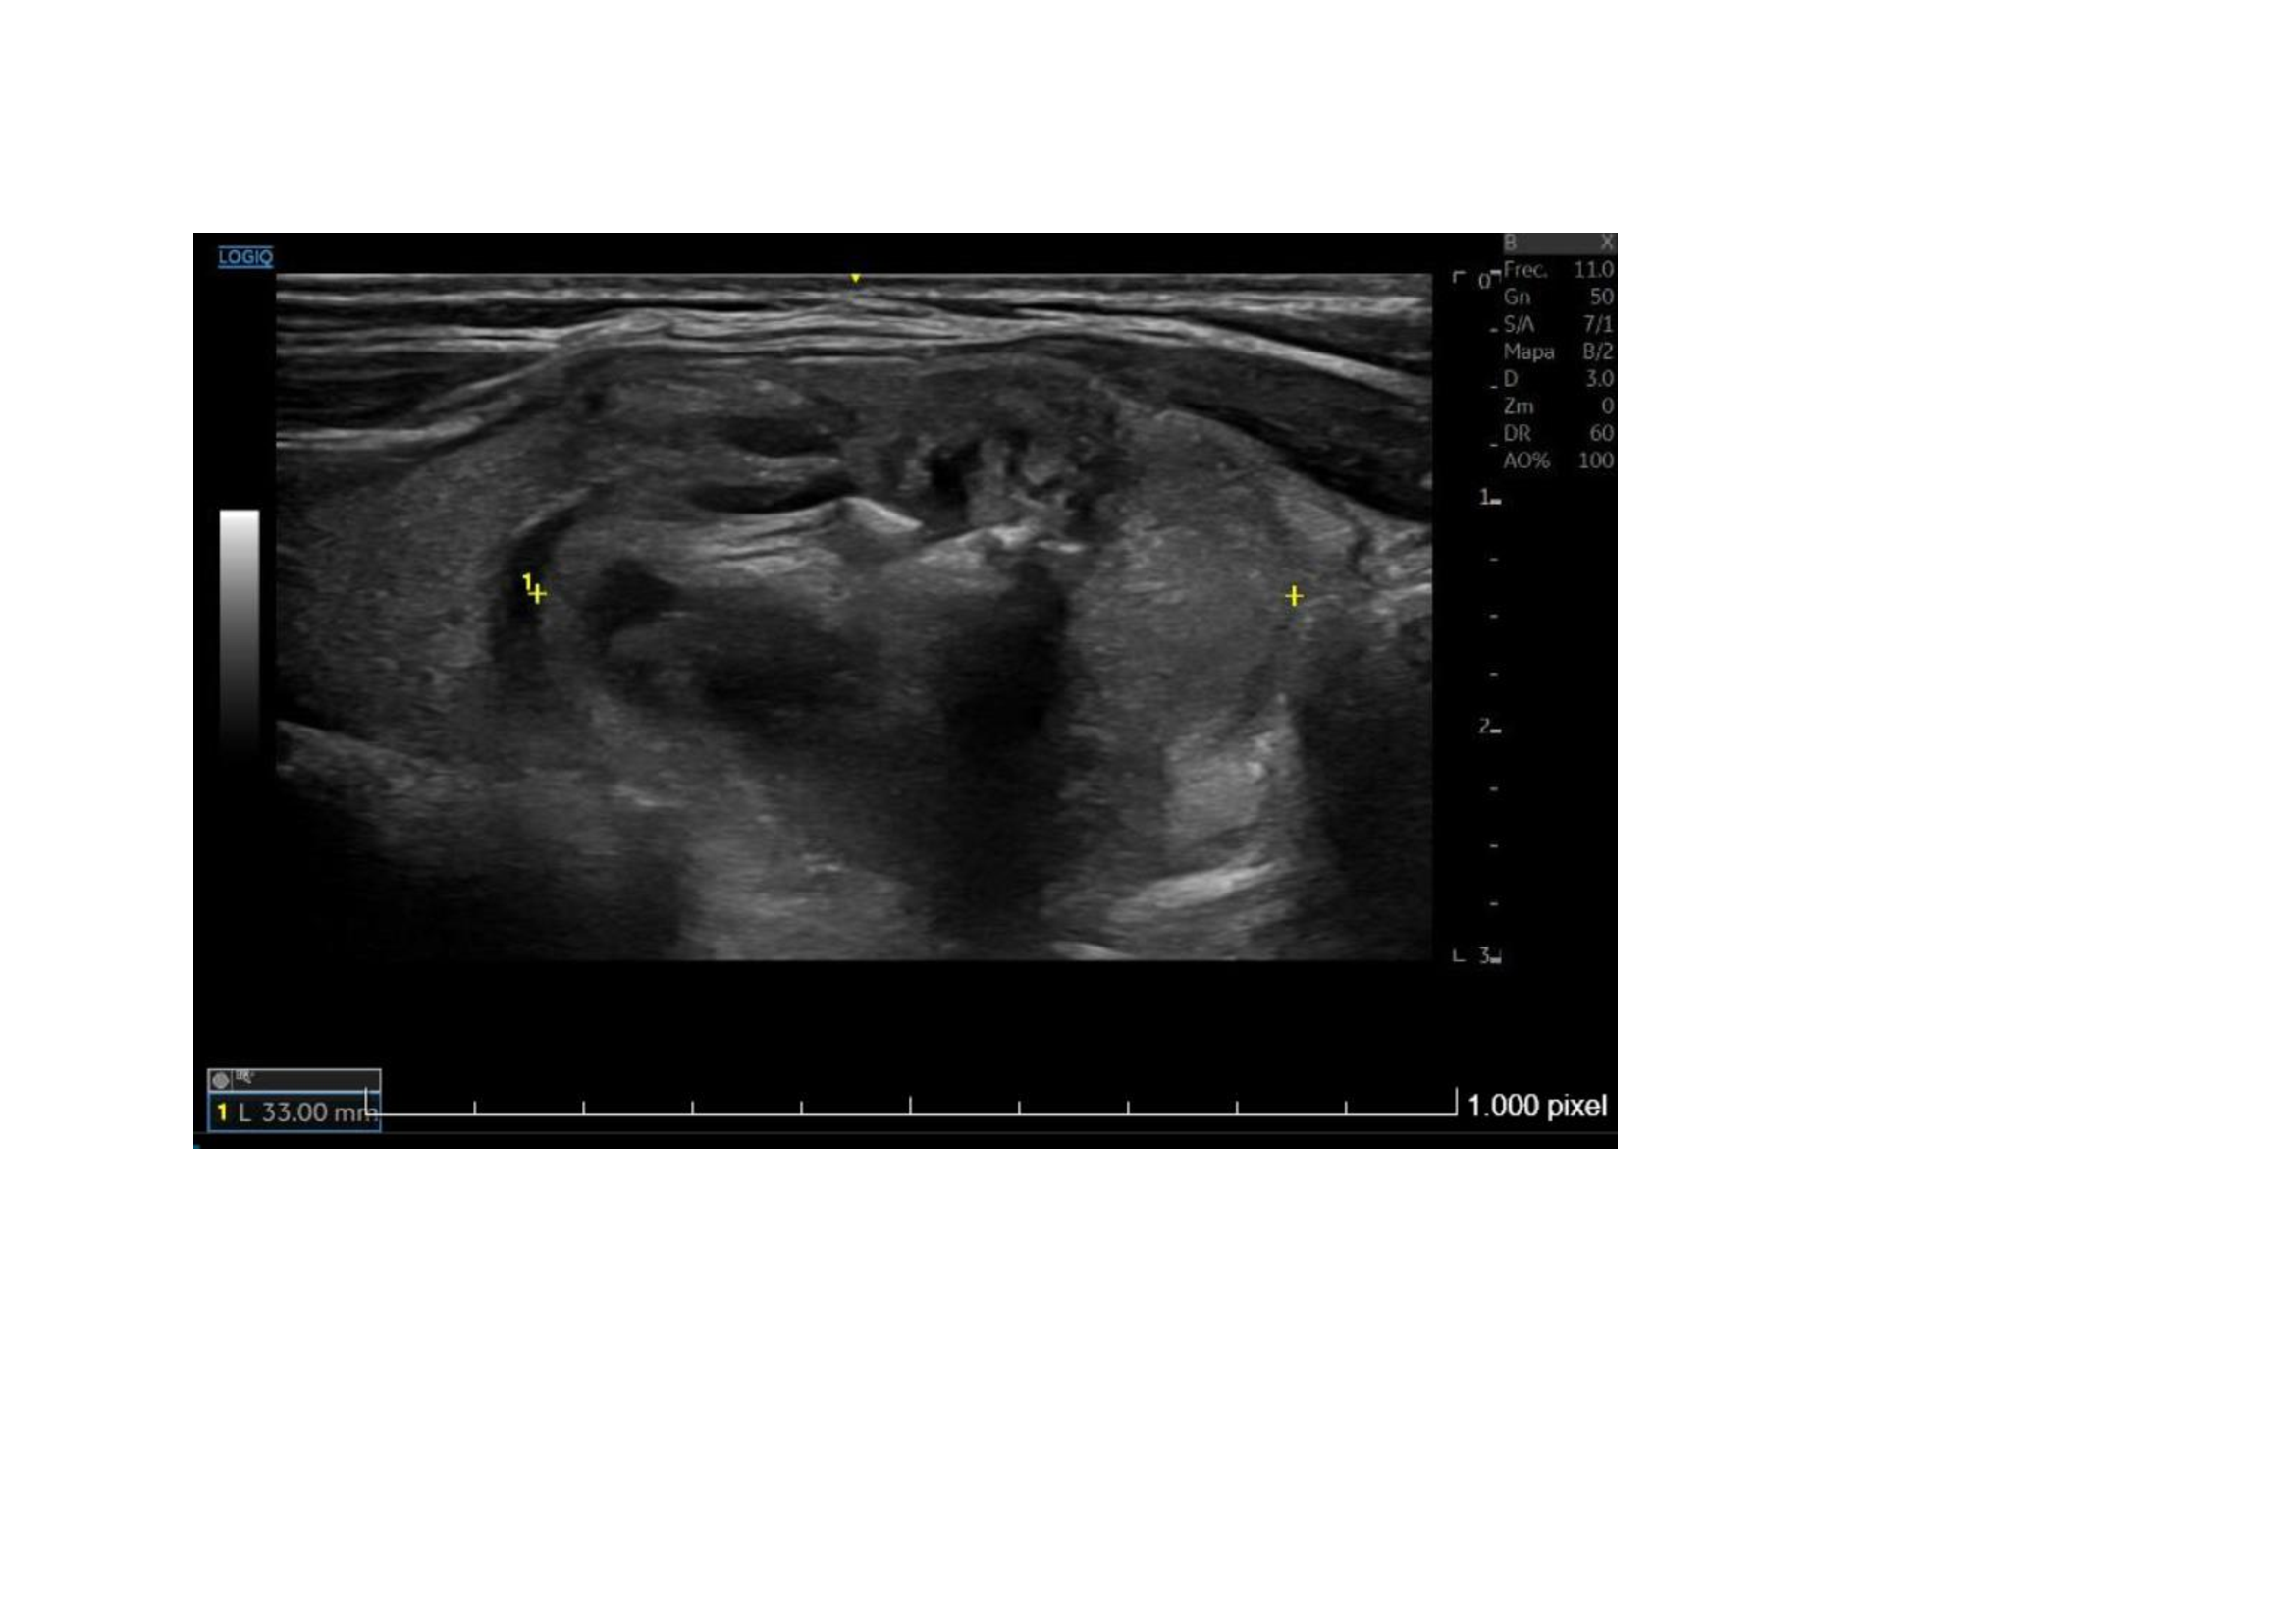

Ecografía clínica: En lóbulo tiroideo derecho observamos nódulo mixto sólido-quístico, de 11,8 x 14,5 x 15,4 mm, de bordes bien delimitados mayoritariamente hipoecogénico, parcialmente tabicado a nivel inferomedial, más alto que ancho con micro calcificaciones en su interior. TIRADS 5.

Ecografía Hospital: Lóbulo tiroideo derecho aumentado de tamaño (2,2 cm de diámetro anteroposteior), por la presencia de un nódulo sólido, heterogéneo, levemente hipoecoico, bien definido, con áreas de degeneración quística y calcificaciones groseras en su interior, de 22 x 21 x 33 mm. Resto del tiroides sin alteraciones. No se aprecian adenopatías cervicales. Glándulas salivares sin alteraciones. Conclusión: Nódulo en lóbulo tiroideo derecho, único, TIRADS 4.